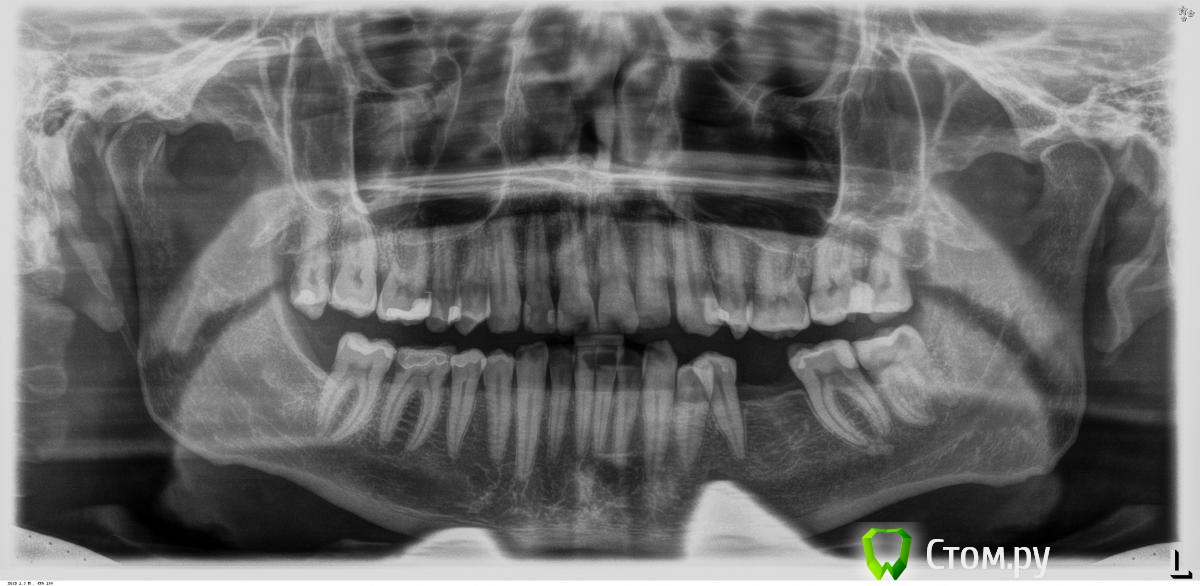

M@estro Опубликовано 4 сентября, 2014 Поделиться Опубликовано 4 сентября, 2014 а что вы хотите увидеть на снимке? Уровень костной ткани. 3 Ссылка на комментарий

Dr.Sham Опубликовано 24 сентября, 2014 Автор Поделиться Опубликовано 24 сентября, 2014 Ссылка на комментарий

Ст@ся Опубликовано 24 сентября, 2014 Поделиться Опубликовано 24 сентября, 2014 Судя по РГ можно решить хирургическим функциональным удлинением по стандартному протоколу.Если кариес до уровня кости - то зуб на выход. 1 Ссылка на комментарий

faity Опубликовано 24 сентября, 2014 Поделиться Опубликовано 24 сентября, 2014 rustal.jpgудаление всех 8-х, замена всех реставраций брекеты, имплантация3.7- прицельник, скорее всего под снос Ссылка на комментарий

Dr.Sham Опубликовано 26 сентября, 2014 Автор Поделиться Опубликовано 26 сентября, 2014 (изменено) Судя по РГ можно решить хирургическим функциональным удлинением по стандартному протоколу.Если кариес до уровня кости - то зуб на выход. хирургическое функциональное удлинение в апроксимальной зоне...на курсе Расперини говорил и показывал, что в такой ситуации нужно резать десну и кость вестибулярно, получится, что корни оголятся и что тогда....десну можно расщепить и перенести апикальнее, чтобы кератинизированная осталась, но бифуркация? вестибулярно отрежем, а небно? Изменено 26 сентября, 2014 пользователем Dr.Sham Ссылка на комментарий

SDC Опубликовано 26 сентября, 2014 Поделиться Опубликовано 26 сентября, 2014 (изменено) вопрос иначе поставлю, кто готов взяться за эту работу с сохранением зубов и долгосрочным прогнозом? в С-Пб)Осуществите иной план:удаление 8-го и спокойная реставрация 7-го через 2-3 недели Изменено 26 сентября, 2014 пользователем SDC 1 Ссылка на комментарий